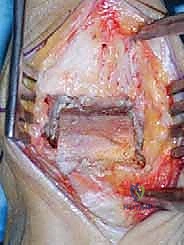

2. إزالة الزوائد العظمية وتحرير المفصل

يتم إزالة النتوءات العظمية (Osteophytes) التي تسبب الألم وتحد من الحركة، وتحرير الأنسجة المتليفة لاستعادة المرونة الأولية للمفصل.

1. الشق الجراحي والوصول للمفصل

يقوم الجراح بإجراء شق أمامي طولي (Anterior Approach) في منتصف الكاحل. يتم إبعاد الأوتار والأوعية الدموية والأعصاب بعناية فائقة (هنا تتجلى أهمية مهارات الجراحة الدقيقة التي يمتلكها الدكتور هطيف) للوصول إلى محفظة المفصل.